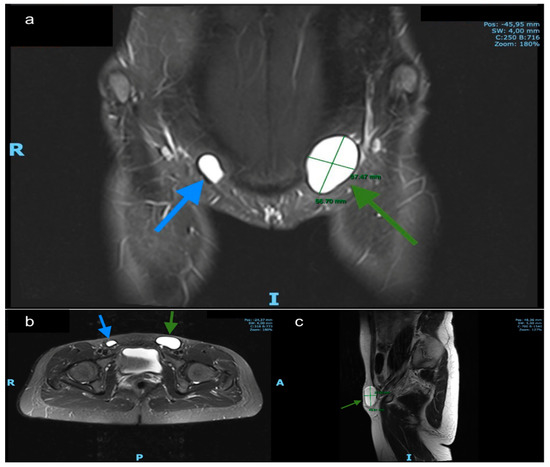

| Diagnostic Study | Ultrasound | Ultrasound | Ultrasound | Ultrasound and magnetic resonance imaging (MRI) | Ultrasound | MRI |

| Type of Nuck hydrocele | type 2 | type 2 | type 2 | type 1 | type 3 | type 2 |